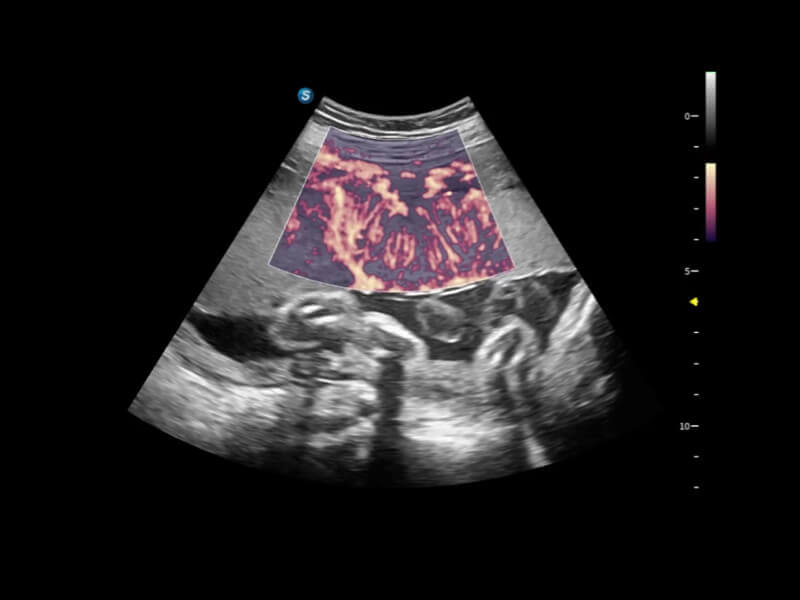

• Bright Flow

Bright Flow bietet eine 3D-ähnliche Farb-Doppler-Flow-Visualisierung ohne den Einsatz eines Volumenwandlers, wodurch die Grenzdefinition der Gefäßwände verstärkt wird.